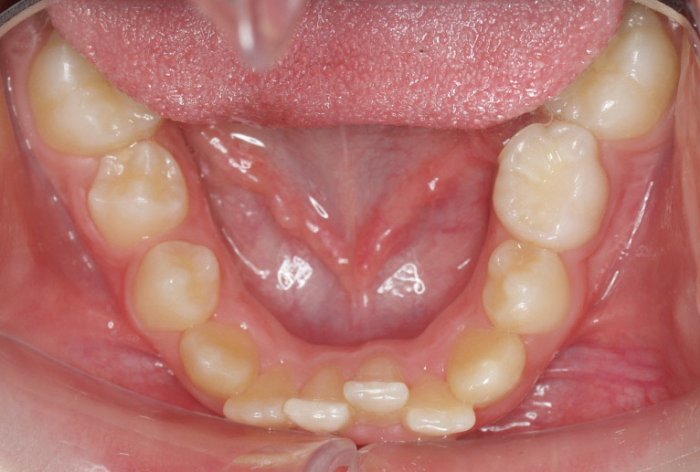

Un “diastema” es una separación extraordinariamente grande entre dos o más dientes. La mayoría de las veces, el diastema aparece entre los dos dientes delanteros superiores. Muchos niños tienen diastema cuando se les caen los dientes de leche, pero en la mayoría de los casos esta distancia desaparece cuando salen los dientes permanentes.

Los diastemas pueden deberse a una diferencia en los tamaños de los dientes, a la falta de algún diente o a que el frenillo labial sea demasiado grande. El frenillo labial es el tejido que va desde el interior del labio hasta la encía, en el lugar donde se sitúan los dos dientes delanteros superiores. Los diastemas también pueden deberse a problemas en la alineación de la boca, como la sobremordida horizontal o la protrusión de los dientes1.